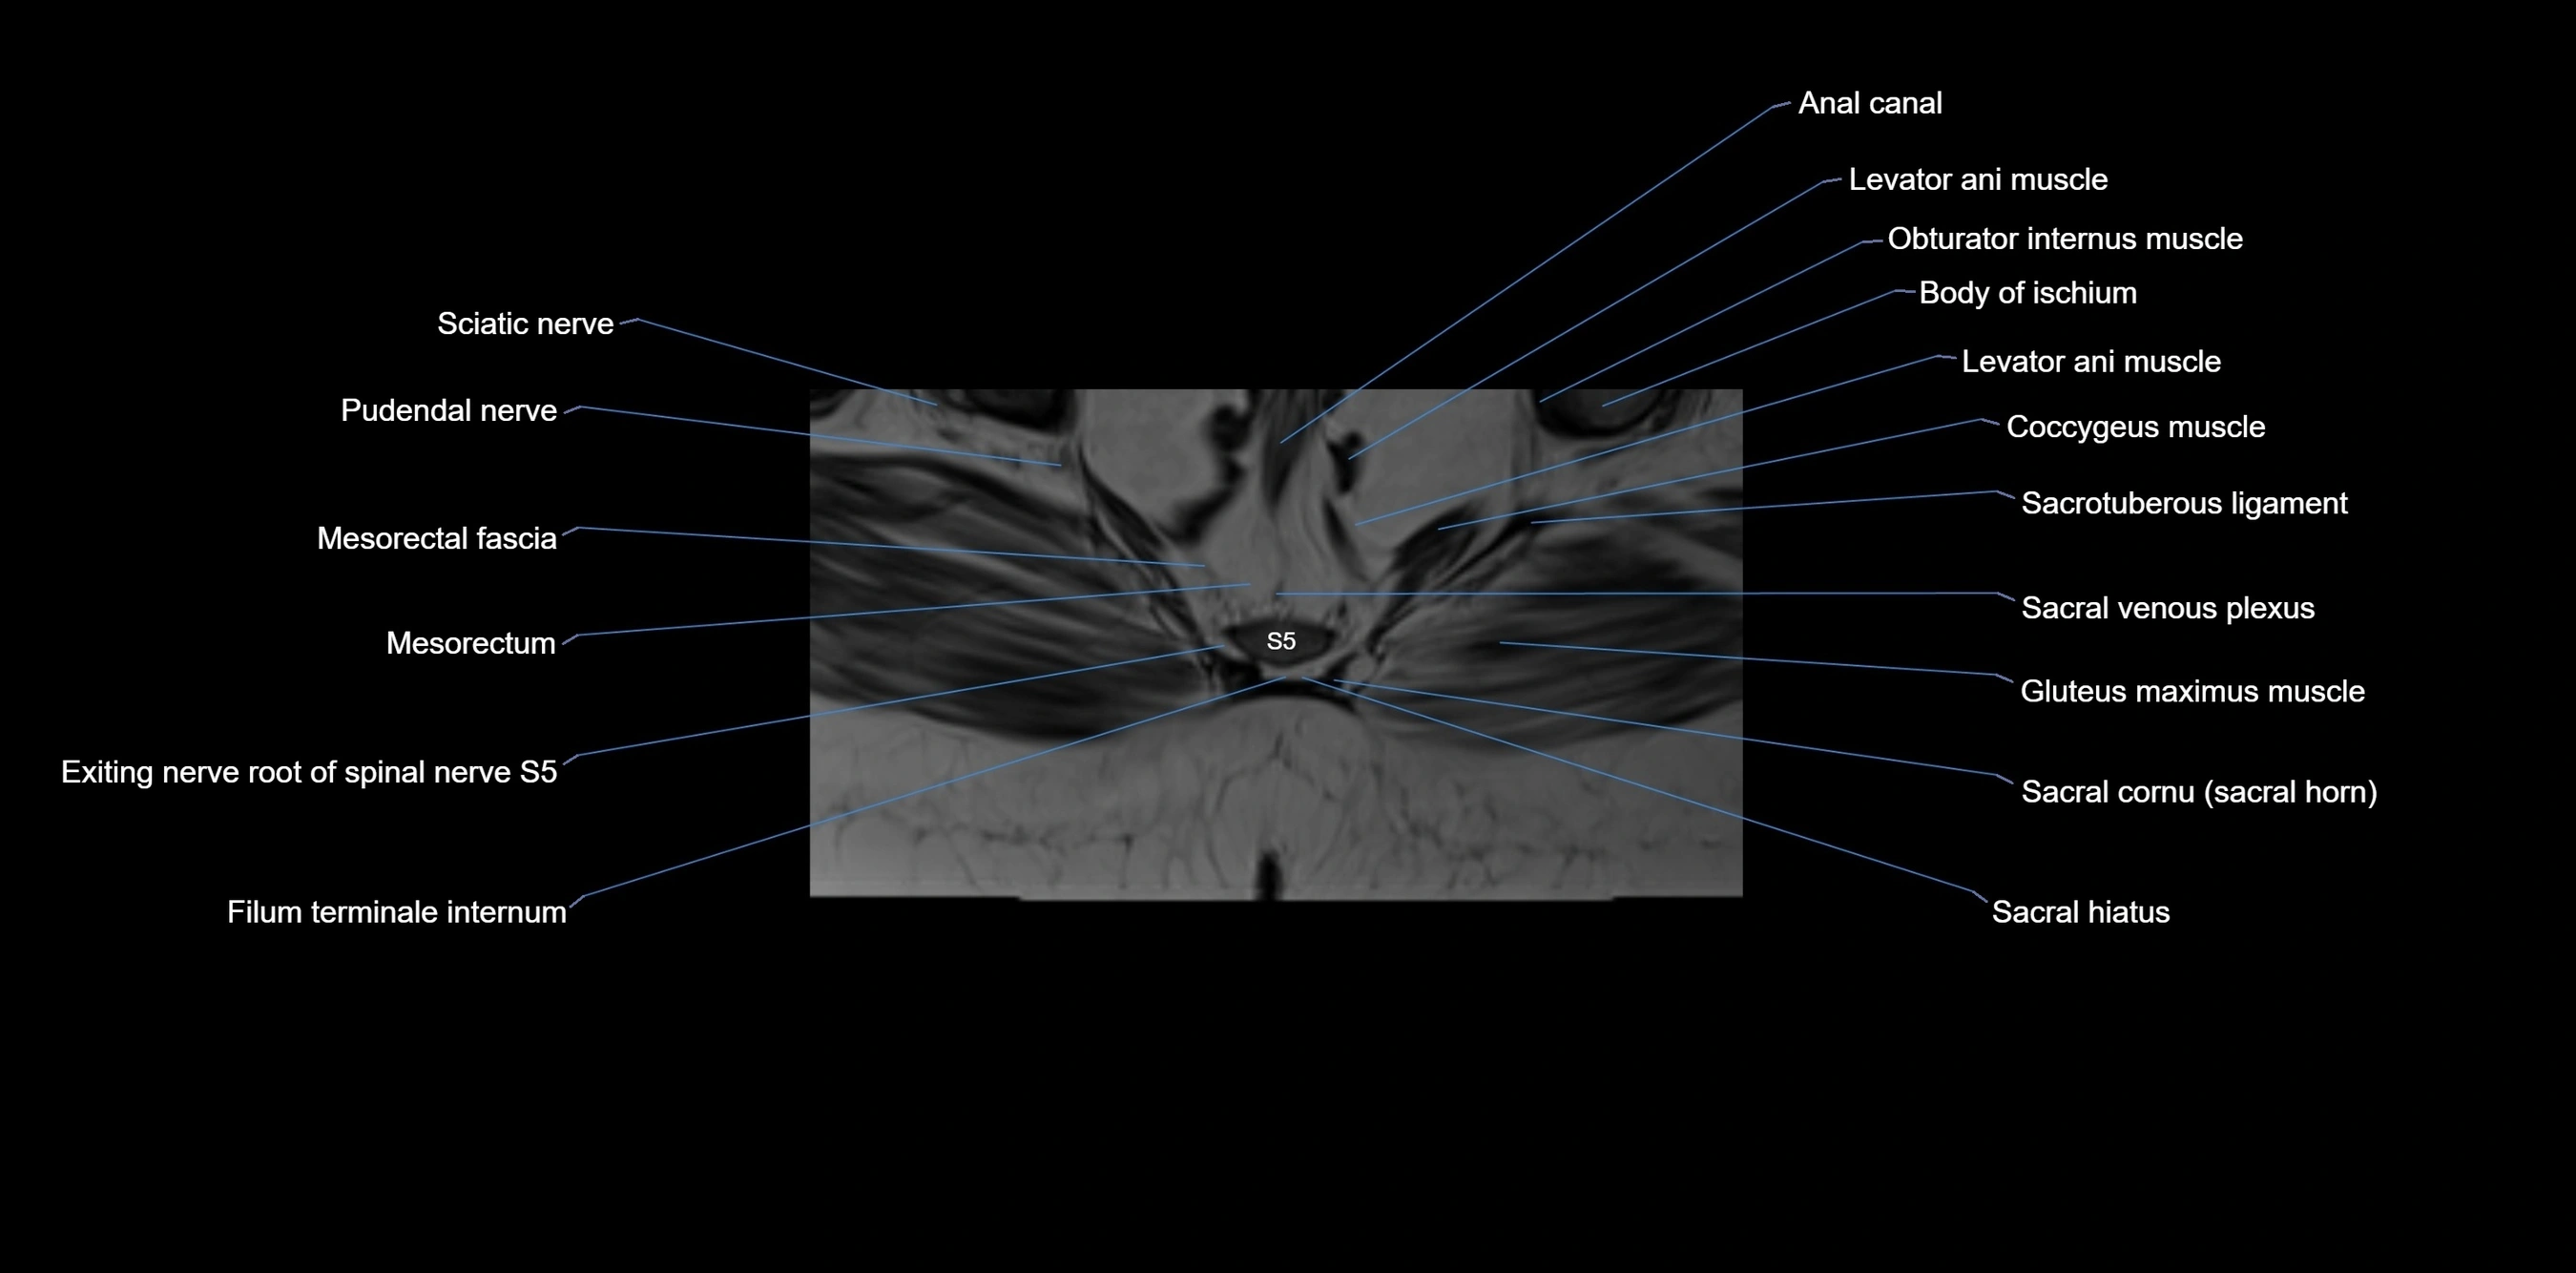

MRI image

image